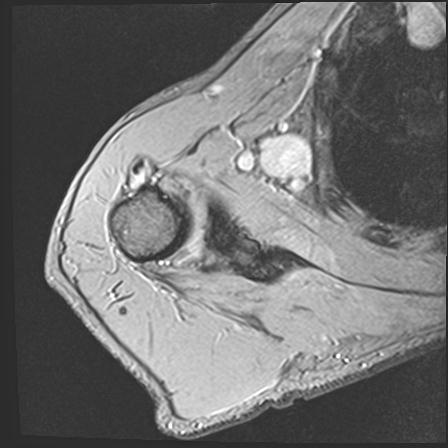

60058 3/9 11/4 右肩 2R+MRI 73歳男性 肩腱板損傷